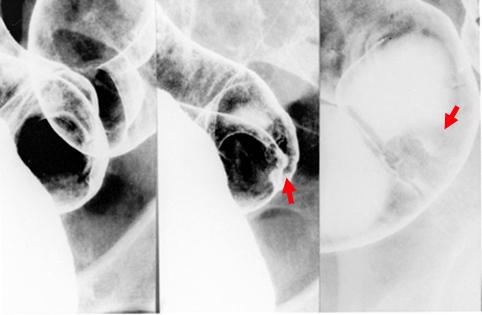

根据中心凹陷存在不整和层段诊断为sm被浸润的表面隆起凹陷型(IIa+II型)早期大肠癌

大肠/乙状结肠

X线

0型(表在型)/IIa型(IIa+IIc)

15~19

sm